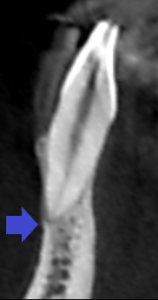

下顎前歯2本歯の歯列矯正治療前の矢状断のCT画像です。

2本とも根の先には、膿の影は見られません。